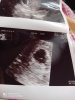

Teraz jest Ci źle i to w pełni zrozumiałe. I pewnie nie widzisz większych nadziei. Ale naprawdę pomyśl, że masz 50% szans na dziecko. Postaraj się odpoczywać bo stres nie jest dobrym doradcą. Ściskam cię mocno bo dokładnie to samo przeżywałam dwa tygodnie temu. To mój pęcherzyk z wtedy, zauważ że jest "bardziej" pusty.

Załączniki

• IMG_20200804_150952.jpg

IMG_20200804_150952.jpg

1,8 MB · Wyświetleń: 79